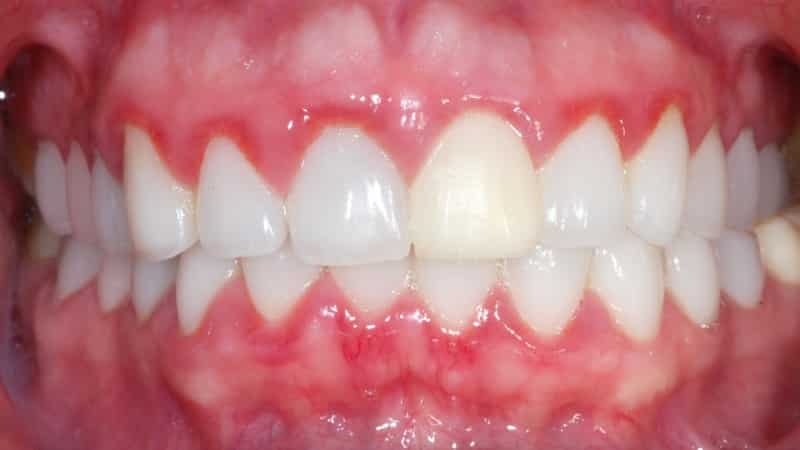

В некоторых случаях у ребенка может наблюдаться повышение температуры. Врач сможет легко установить диагноз всего лишь по результатам визуального осмотра. Гингивит всегда проявляется покраснением десен, отечностью тканей, образованием ранок и язв, а также кровоточивостью.

Атрофическая форма заболевания возникает из-за некачественного стоматологического лечения или наличия аномалий. Воспалительный процесс выражен не так сильно, цвет десен остается прежним, и ребенок не жалуется на боль. Тем не менее, ткани десен значительно страдают. Со временем может обнажаться шейка зуба, что приводит к неприятным ощущениям. Зубы становятся чувствительными к горячей и холодной пище.